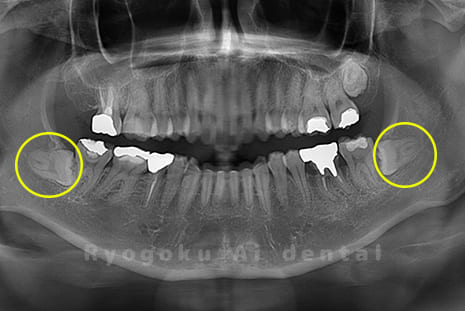

Case02

-

- 原因

- 下顎の水平埋伏智歯

- 治療内容

- 下顎の水平埋伏智歯を抜歯

<リスク・副作用>

手術後は痛み、腫れ、痺れなどの副作用が生じる場合があります。